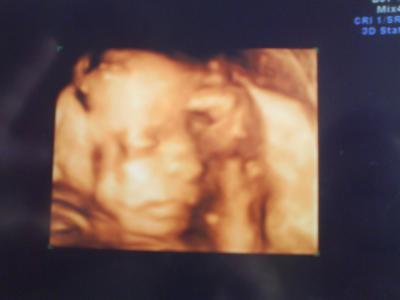

Und ich hab das schönste Baby überhaupt und ich bin offiziell heute vordatiert auf den 12.12.2010 und definitiv ein Mädchen, war gar nicht zu verkennen die "kaffeebohne" wie sie sagte. hmm sehr aktiv die Mausi. CA 20cm und 450gramm. komisch das die hebi neulich beim US was anderes sagte. kann leider mit den ganzen messdaten nix anfangen.... sonst würd ichs ausrechnen wie gross sie ist.

Bild zu Bin zurück von der FD :D - Forum für Dezember - Mamis

Ein SEHR schönes Foto hast du da von deiner Kleinen!!! Du muss FD (Femurdurchmesser) x 7 nehmen. So viel weiß ich nur. Aber ist doch super dass alles ok ist mit der Kleinen!!! Wünsche dir einen schönen Tag! Lg Kirsten

Herzlichen Glückwunsch zum Mädel!!! Richtig süßes Bild von der Prinzessin. LG - Dörte